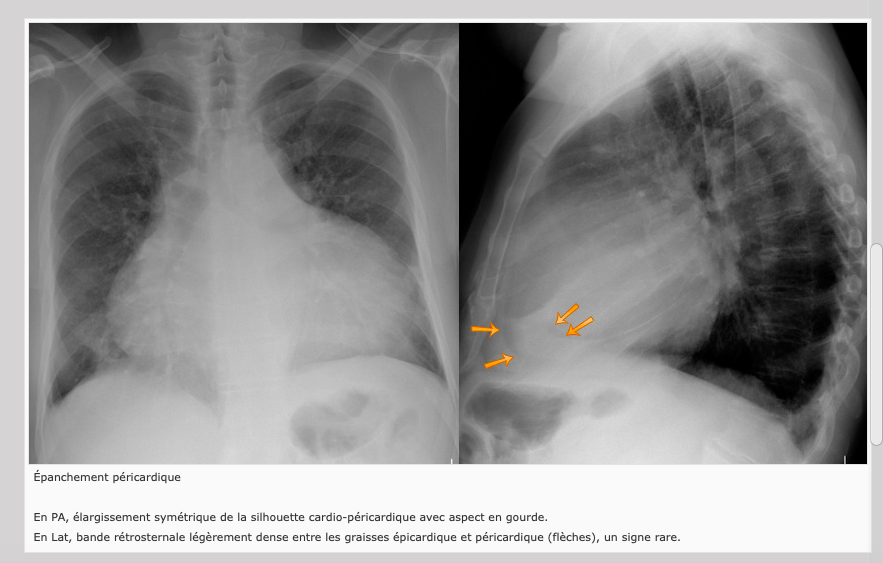

Épanchement pleural